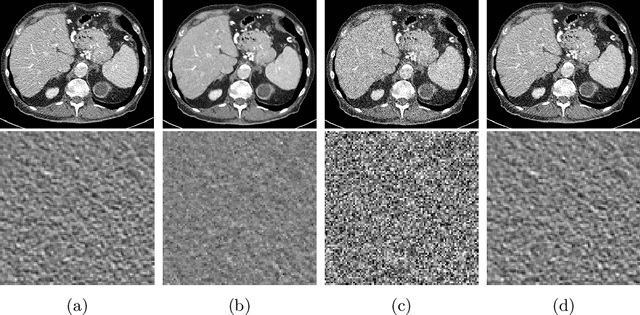

Abstract:Recently, Self-supervised learning methods able to perform image denoising without ground truth labels have been proposed. These methods create low-quality images by adding random or Gaussian noise to images and then train a model for denoising. Ideally, it would be beneficial if one can generate high-quality CT images with only a few training samples via self-supervision. However, the performance of CT denoising is generally limited due to the complexity of CT noise. To address this problem, we propose a novel self-supervised learning-based CT denoising method. In particular, we train pre-train CT denoising and noise models that can predict CT noise from Low-dose CT (LDCT) using available LDCT and Normal-dose CT (NDCT) pairs. For a given test LDCT, we generate Pseudo-LDCT and NDCT pairs using the pre-trained denoising and noise models and then update the parameters of the denoising model using these pairs to remove noise in the test LDCT. To make realistic Pseudo LDCT, we train multiple noise models from individual images and generate the noise using the ensemble of noise models. We evaluate our method on the 2016 AAPM Low-Dose CT Grand Challenge dataset. The proposed ensemble noise model can generate realistic CT noise, and thus our method significantly improves the denoising performance existing denoising models trained by supervised- and self-supervised learning.